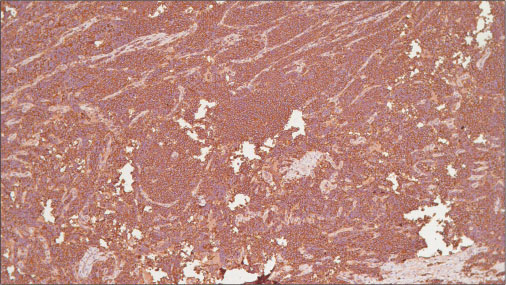

Of the 11 patients, four patients had ES, five extraosseous Ewing?s sarcoma (EES), one with primitive neuroectodermal tumor (PNET), and one with Askin?s tumor. Two had associated comorbidities, spherocytosis and bronchial asthma. The patient with Askin?s tumor developed scalp and leptomeningeal metastasis and succumbed. All 11 patients were IHC proven, and all of them were CD99 positive [Figure 1], [2]. Five patients were vimentin positive and two were neuron-specific enolase positive along with CD99 (MIC-2). Five patients had multiple metastases at the time of presentations, of which four poorly responded to chemotherapy and succumbed very early during the course inspite of compliant treatment, while one patient still continues to follow-up. The two patients who had paraspinal ES developed acute-onset paraparesis and incontinence which progressed to paraplegia within a couple of weeks. Among them, the child was lost to treatment follow-up, while the other patient underwent debulking surgery and was initiated on adjuvant chemotherapy but died after 2 weeks. There were two patients who had a lag time of >2 years to develop metastasis who are still on regular review [Table 1]. Of the 11 patients, only four continue to review in our outpatient clinic while six succumbed and one patient was lost to treatment follow-up. Of the 11 patients, only one patient received radiation to primary site after six courses of chemotherapy, but yet after 3 months, he developed orbital metastases which were cytologically proven.

|?Figure. 3? Immunostain showing diffuse positivity of MIC-2